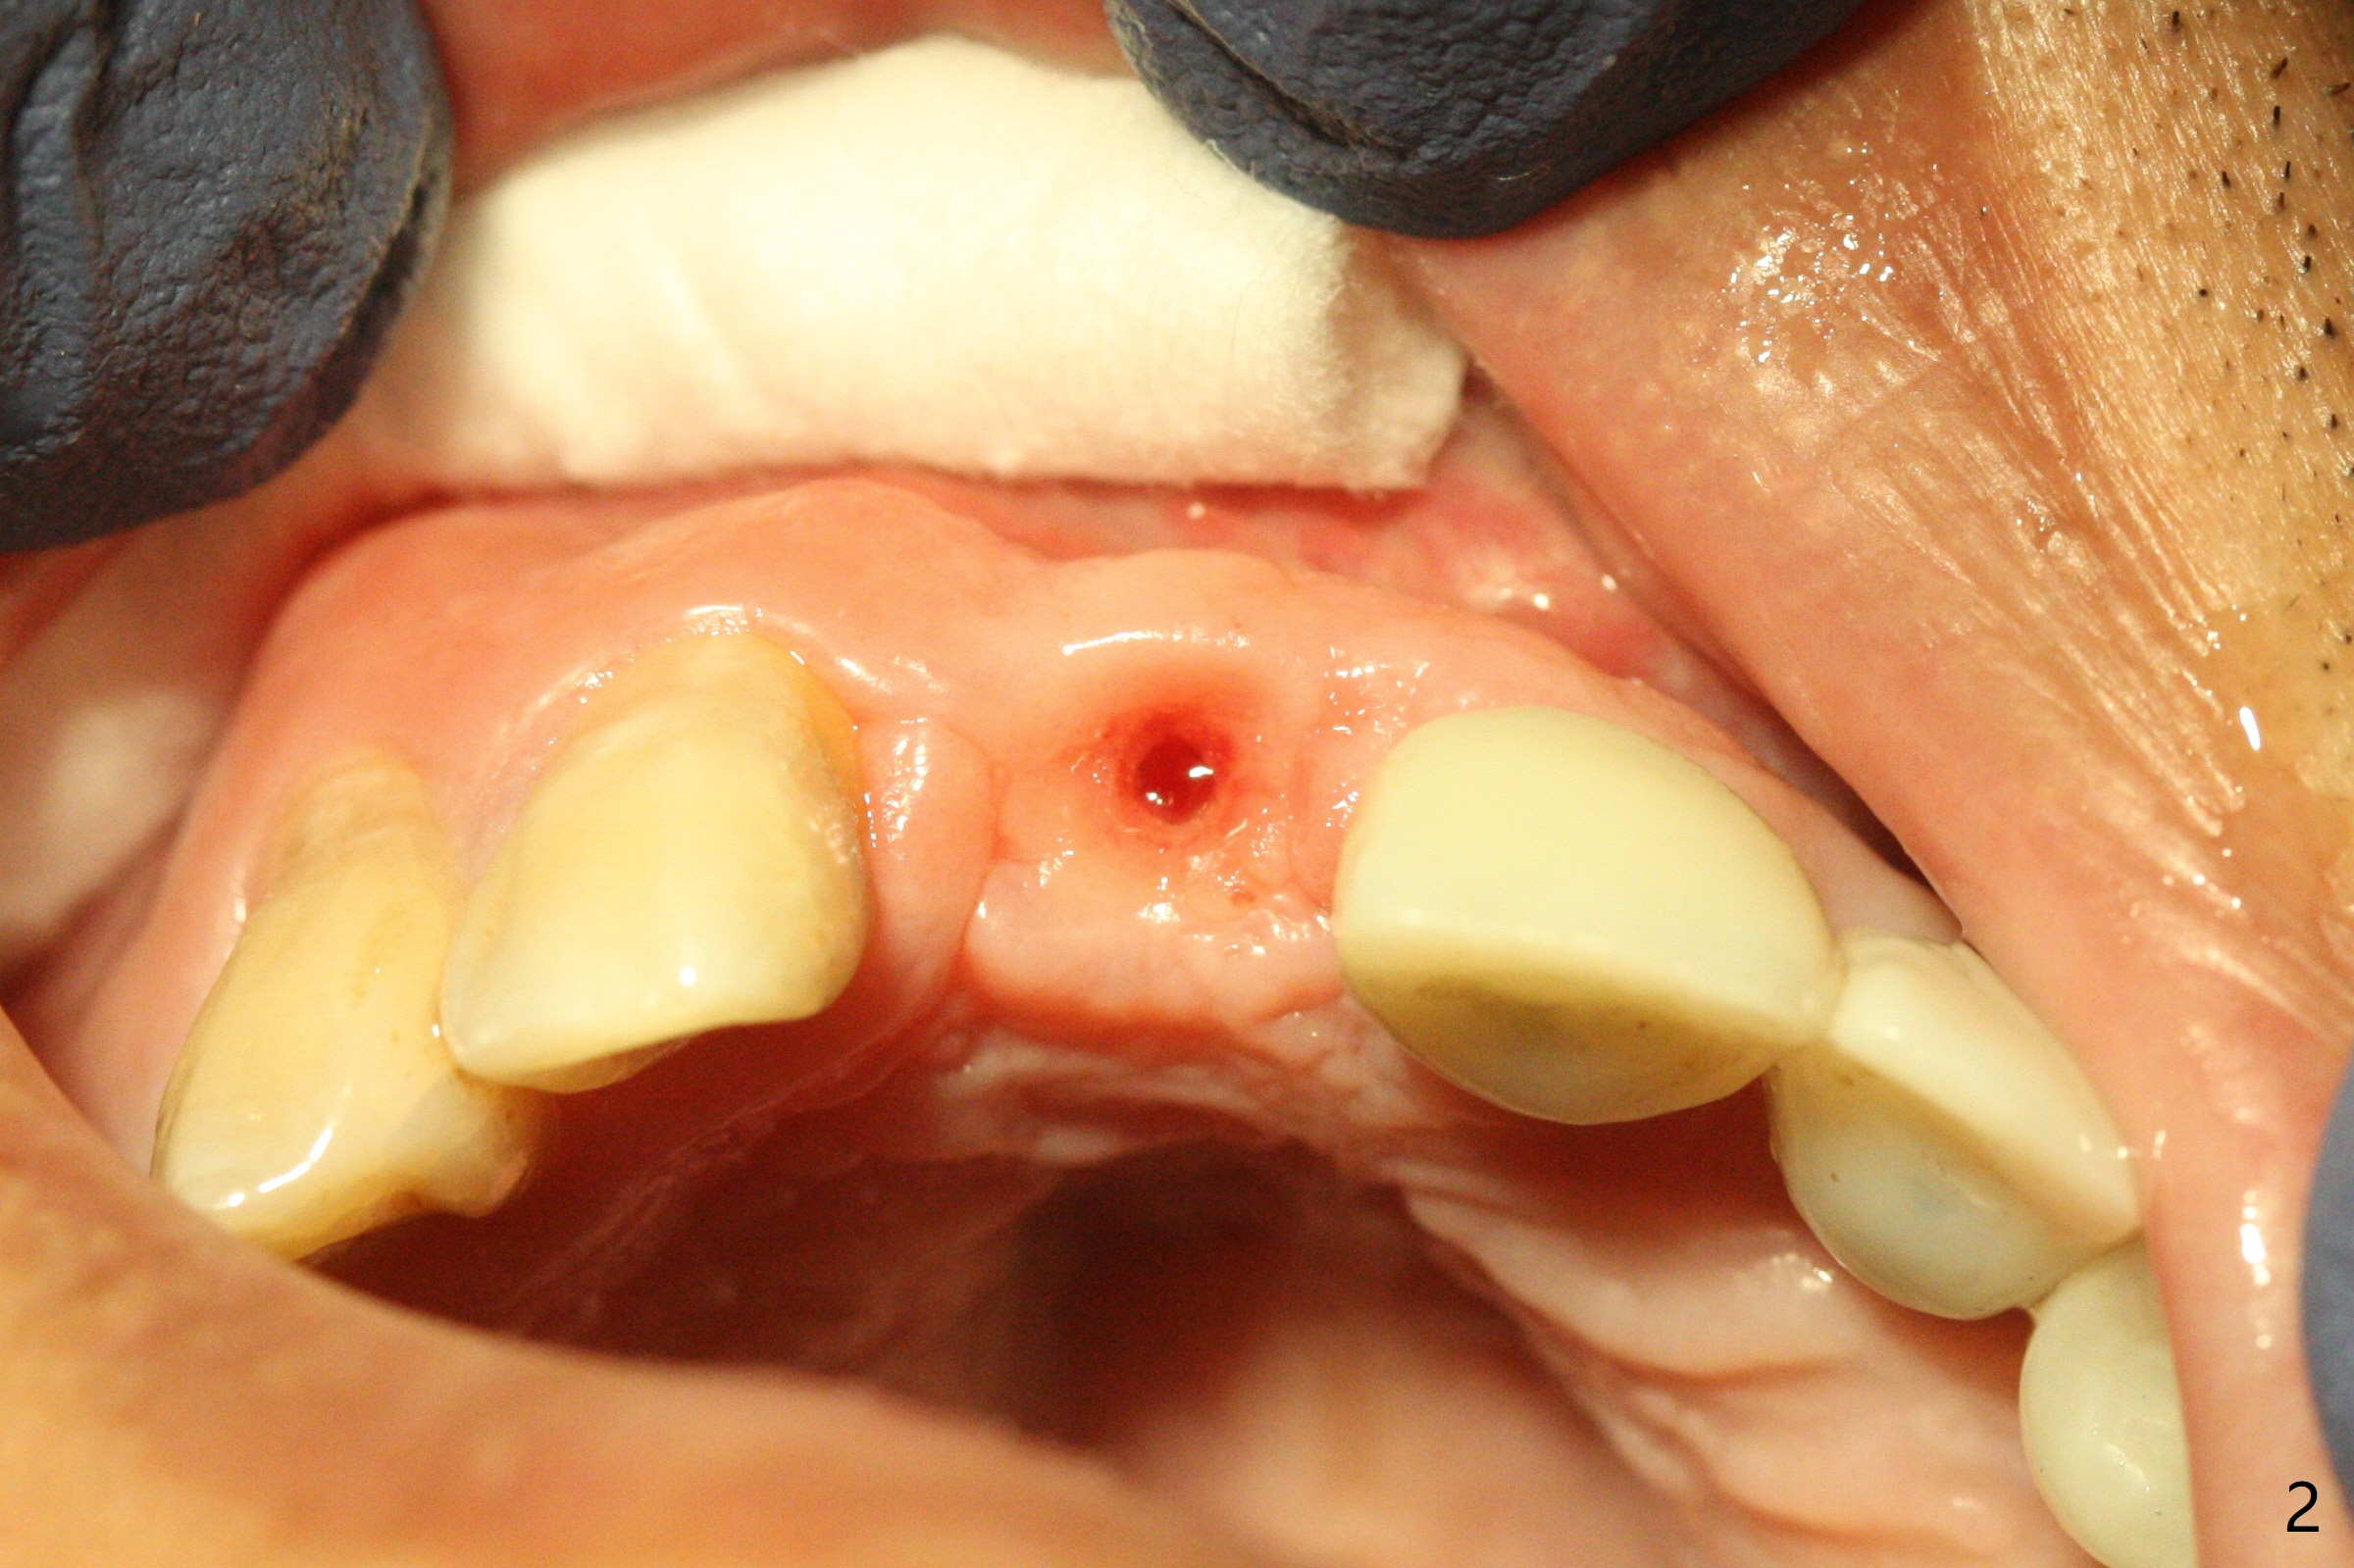

A 43-year-old man has 6 of 1-piece implants in the maxilla (#8-13). His daughter's head hits his upper anterior teeth 7 months post cementation. Exam shows that the tooth #7 has mild percussion. Nine months later the implant crown at #8 becomes displaced and loose when he bites apple (Fig.1 arrow). Forceps are used to remove the crown, leaving a concave implant site (Fig.2). After the crown is bonded to the neighboring tooth/implant crown (Fig.3 *), the patient feels pain from the neighboring tooth. The alveolus is 4.3 mm wide (Fig.4 (2.9 mm preop)), allowing 2.5 or 3.0 mm immediate implant re-placement (Fig.5). A 2.0/3.0 mm trephine bur will be used for implant removal. Try to place the new implant slightly distal to improve the trajectory (Fig.6). Particulate and/or onlay graft is an option. Prepare dummy implants. As planned, the fractured implant is removed by using a 2.0/3.0 mm trephine bur following incision (Fig.7). After use of Lindamann bur to remove the distal bone, a 3x14(4) mm dummy implant is placed with 20 Ncm (Fig.8). A longer implant could be used (3x16(2 or 4) mm), but a 3.5x13 mm 1-piece implant is placed with ~ 50 Ncm after use 3.0 mm drill (Fig.9,10). Allograft is placed around the implant (Fig.9,10 *), followed by Amnion-Chorion membrane and 5-0 PGA sutures (Fig.11). Allograft placed around the implant (Fig.9 *) appears to be able to prevent implant thread exposure 4 months postop (Fig.12). PA is taken when the crown is cemented (Fig.13). Four months postop cementation of #8 crown, the patient returns because of #9 mobility (Fig.14). In fact the implant fractures when the loose crown is removed with forceps; there is bone loss at #10. Bone graft will be placed at #10 with sticky bone (PRFx1), while the implant at #9 is redo. The ridge is wide enough for a 3.5x10 mm implant (Fig.16 (CT taken when #8 implant fractured)). Also prepare Tatum angled 1-piece implant. The 2 mm implant is too thin when occlusion contact at #10-13 is incomplete. The crowns will be redone when the implant at #9 is osteointegrated.